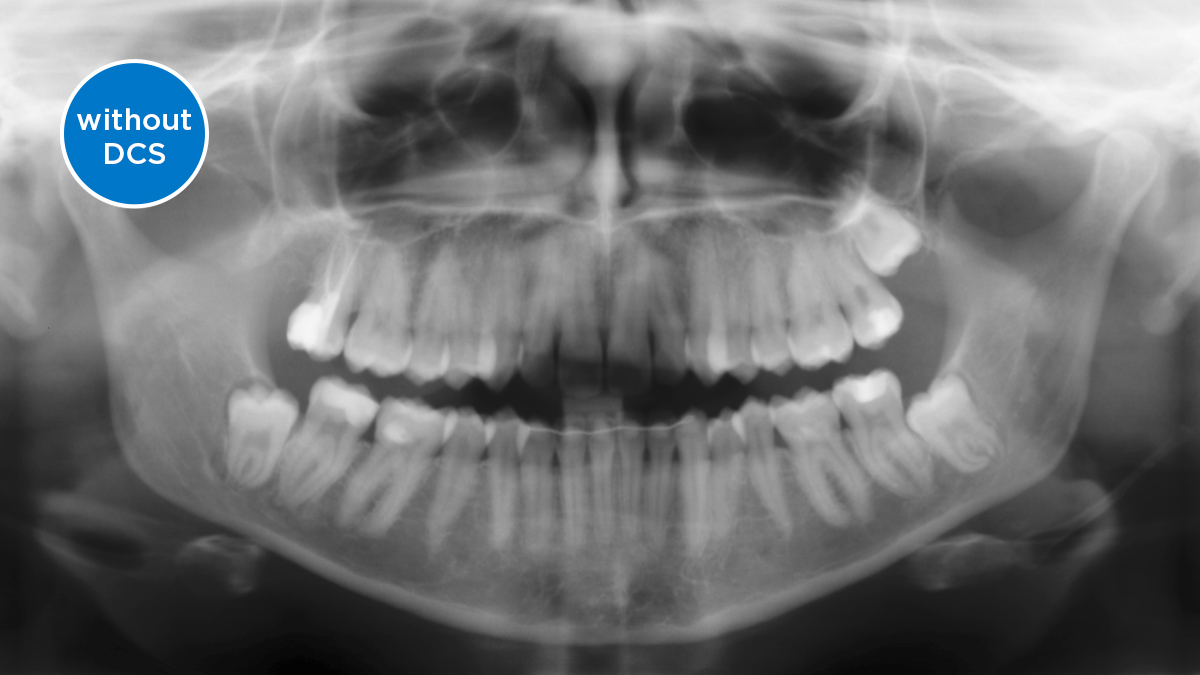

ダイレクト コンバージョン センサー(DCS) 画像診断を次のステージへ

ダイレクト コンバージョン センサー(DCS)によりパノラマ撮影品質を次のステージへ レントゲン画像は直接電気信号に変換されます。そのため、従来のシステムの場合のように、光信号への変換によるデータロスがなく、その結果、低い放射線量でも、非常に鮮明さと高いコントラストを備えた画像が得られます。適切な治療を支援するための正確な診断が可能になります。

サンプル画像は、DCSテクノロジーを使用していない場合と使用した場合のパノラマ画像です。矢印を使用してコントロールを画像上でドラッグすると、DCSセンサーが画質の質と診断の可能性に与える違いを確認できます。